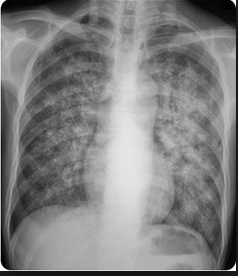

Hilar calcifications: on Xray

coughing: pneumonia

lung with cannon balls: Chest X-ray has patchy alveolar infiltrates/haziness

cannon balls in lung: Lesions or cavities in lungs

lung wall holes, bricks caved in/out: Radiographic images may show either nothing or cavities and/or nodules.

glass tables with cracks: "Ground glass" appearance on chest X-ray